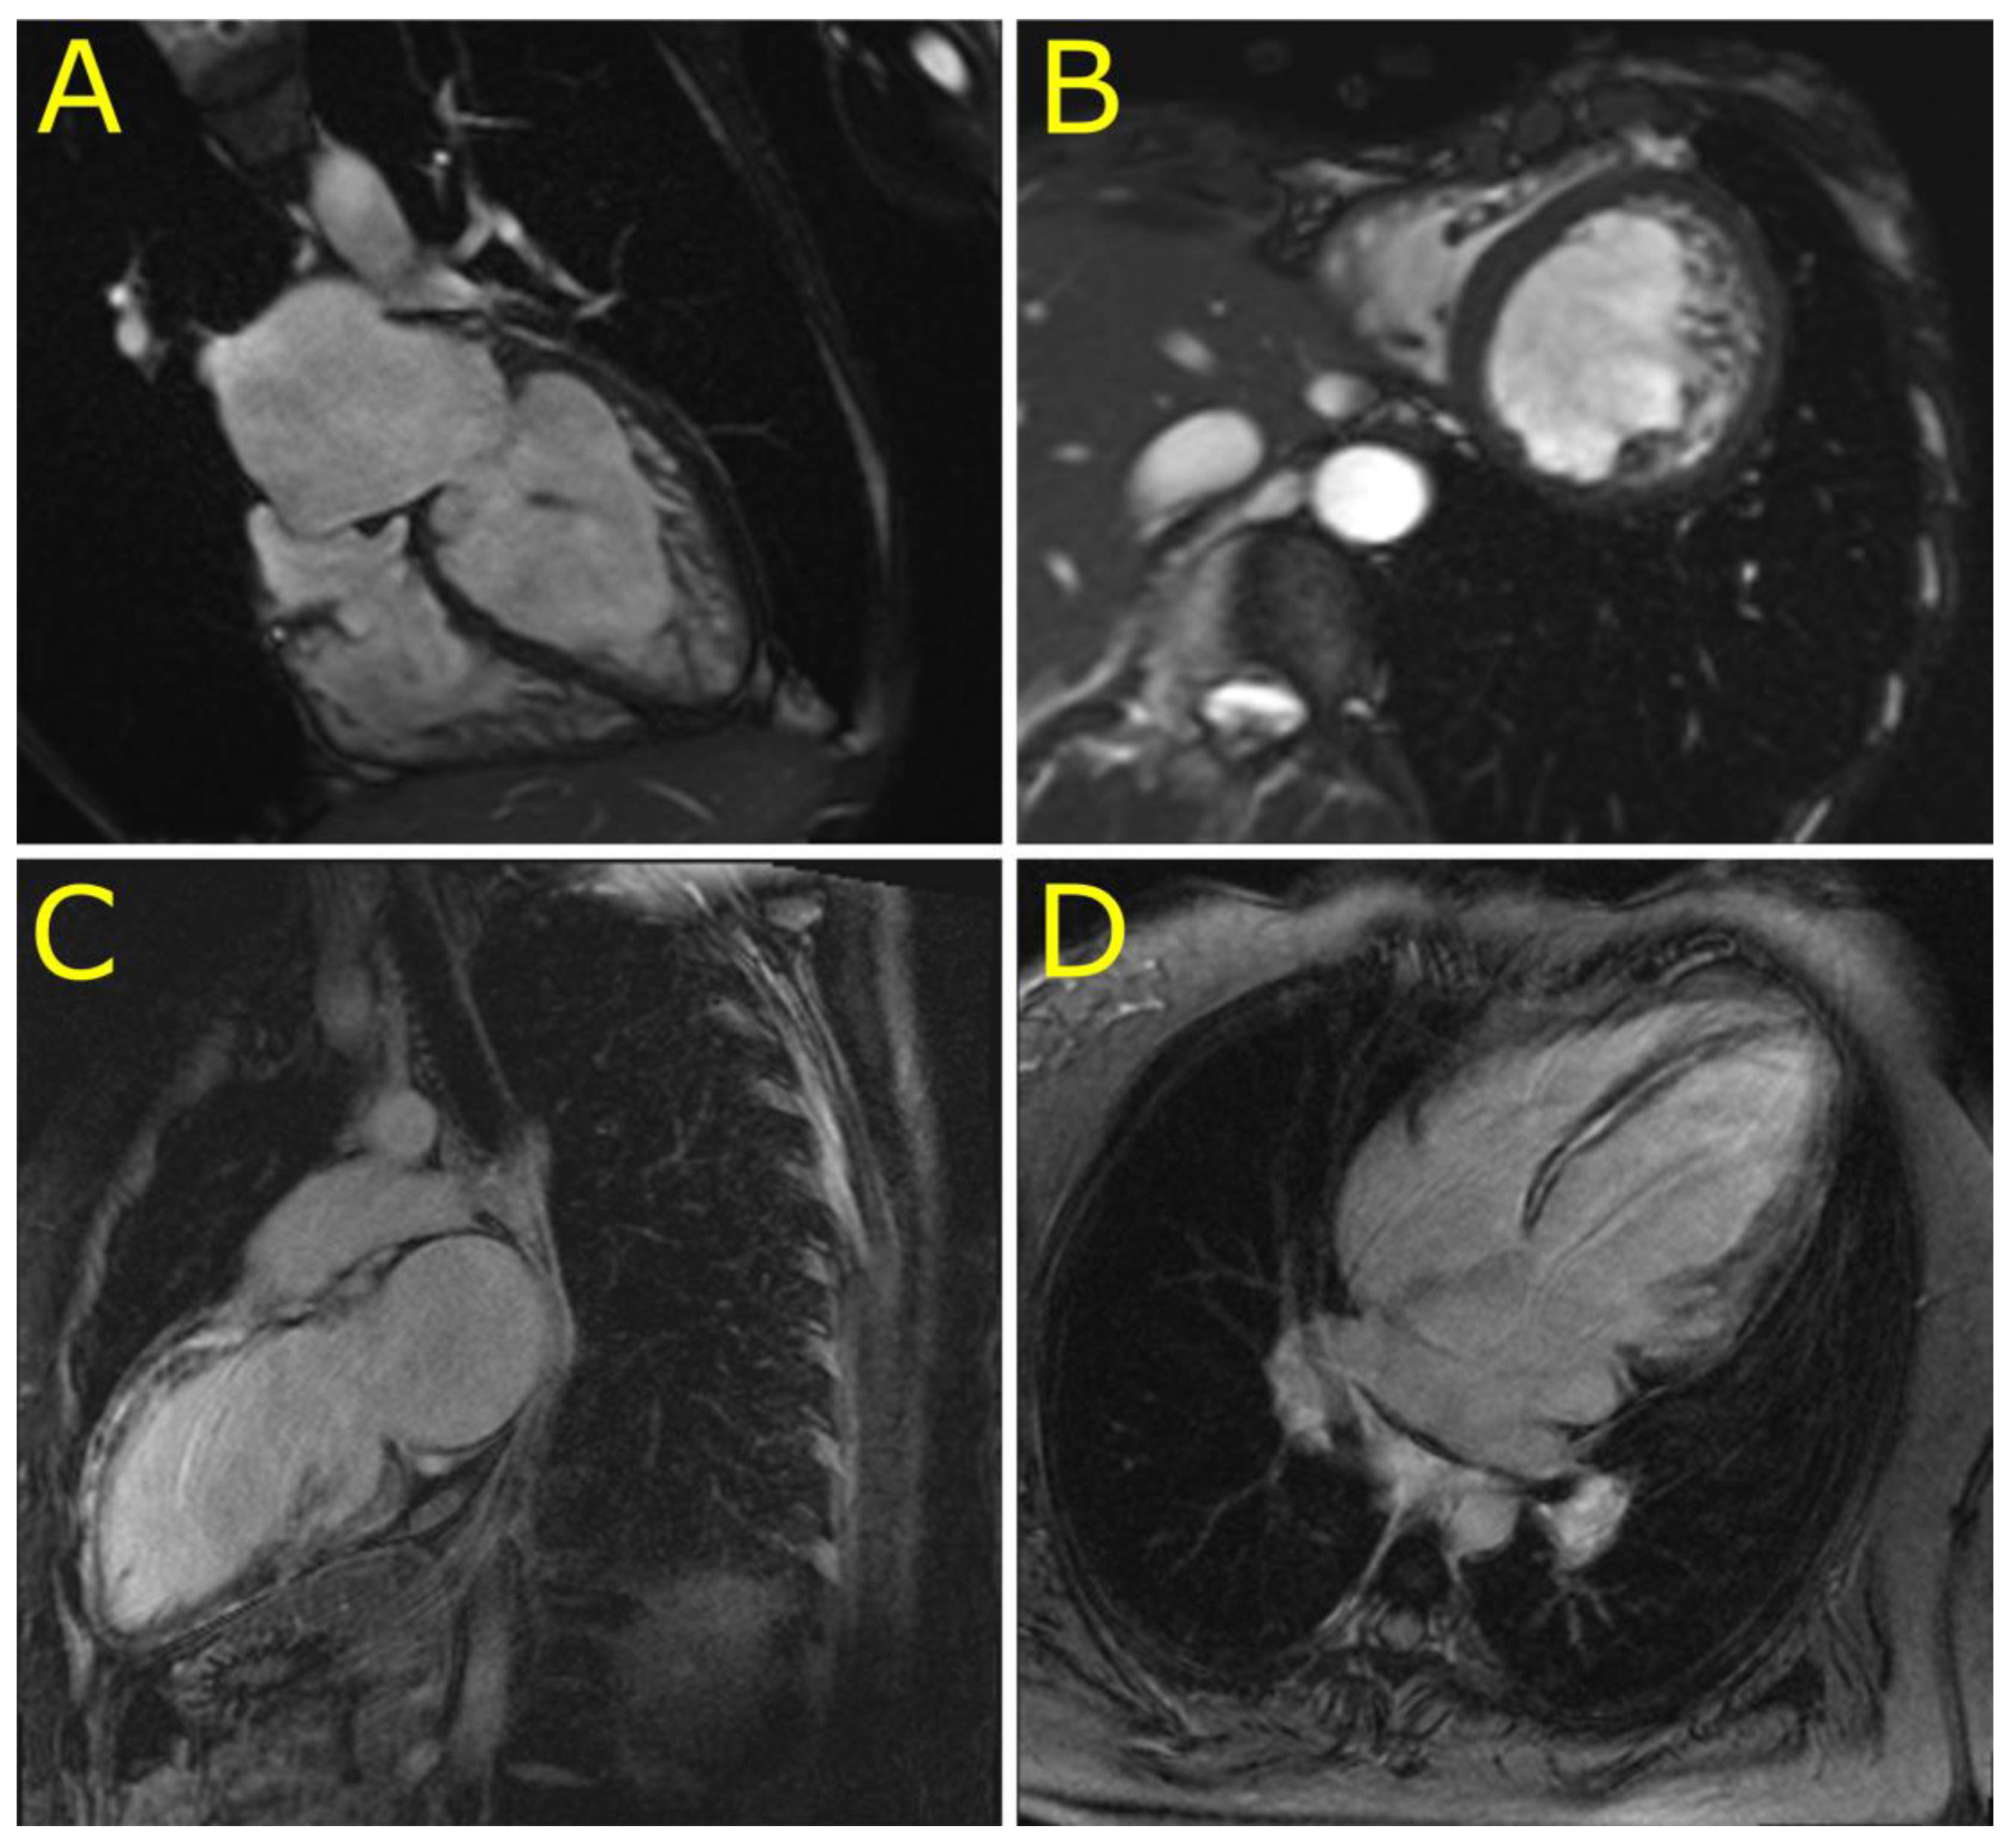

3.2. Phenotypes of Desminopathy

3.3. Morphology of Desminopathy in Myocardial and Skeletal Muscle Samples

4.2. Novel Cardiac Phenotypes of Desminopathy